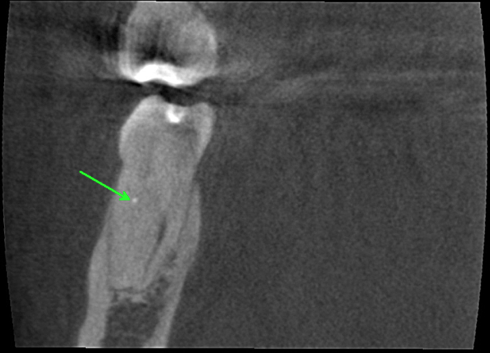

Instead of continuing to trough down the root with an ultrasonic tip or Munce bur, I opted to take an intra-operative CBCT scan with CAOH to provide an accurate road map of where the canals were located. Placing CAOH is helpful as the radio-opacity of the material can be used as a reference point. Additionally the CBCT scan has a ruler function indicates exactly how many millimeters further I need to navigate down the root. Using the scan prevents the unnecessary removal of radicular dentin and facilitates locating the canals.

I have included several different slices from the scan below:

Distal Root, Coronal View, Arrow indicating the lingual split .

Mesial Root, Coronal View, Arrow on CAOH placed at apical extent of trough, indicating that my path was centered within the canal and “on target” to locate the orifice.